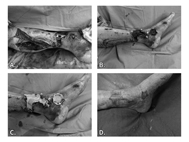

圖二、80歲男性,下肢開放性骨折,造成骨板外露,經局部皮瓣移植(A、B);覆蓋上人工真皮(C);最終達到順利癒合(D)